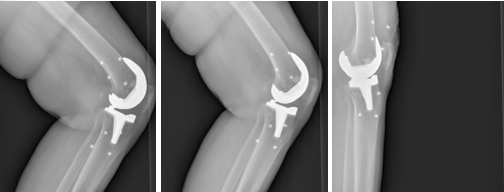

Refer to caption

Figure 5: Tibial plateau-condyle contact points

Figure 5 illustrates the distribution of tibial plateau (TP)–condyle contact distances under different extension angles measured Jennifer’s method [31], where the horizontal and vertical axes represent the medial and lateral distances, respectively. Most points lie below the diagonal (equal medial–lateral distances), indicating asymmetry in TP–condyle contact that supports the presence of leg axis malalignment.

As supplementary evidence, Figure 6 shows the medial–lateral distance difference across frames. Here, the horizontal axis corresponds to frame index and the vertical axis to the medial–lateral difference. The maximum observed deviation exceeds 2 mm, a clinically recognized threshold for diagnosing knee malalignment. The medial-lateral distance can be further visualized by the Figure 7, showing the medial/lateral distance changes by extension angles.

Knee joint instability can also be visualized by Feng’s method [32]. As shown in Figure 8, trajectories are defined by connecting the medial and lateral condyle projection points on the tibial plateau across frames. Color gradients from light to dark denote progression from the initial to the final frame. Notably, the connecting lines shorten as the joint approaches slight hyperextension (Figure 9), a finding corroborated by both the 2D view (Figure 10(a)) and the 3D CBCT reconstruction (Figure 10(b)).